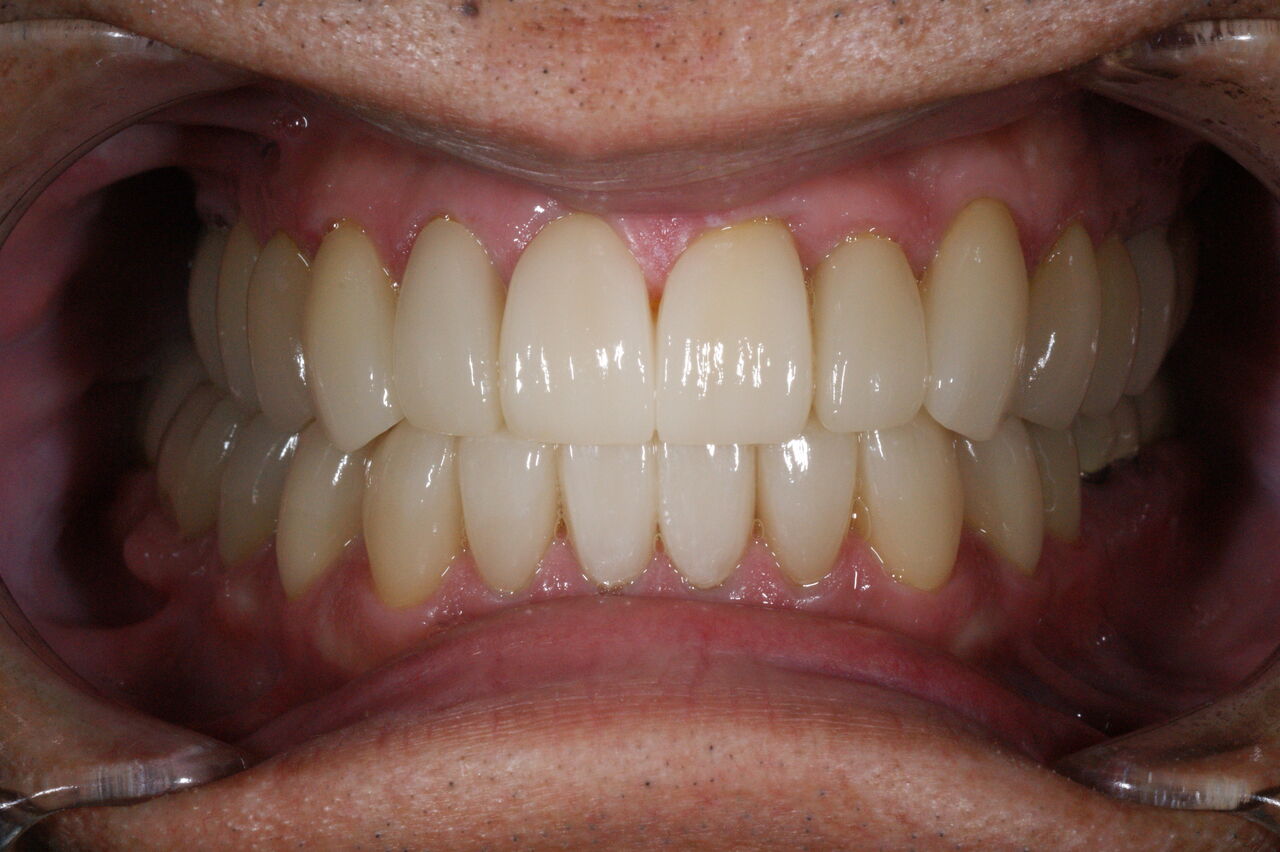

矯正治療終了後、模型を咬合器に付着し診断用ワクシングをしたところ、本来歯牙は咬合調整か小規模の修復処置で済めば極力そのまま使うのが理想ではあるが、長年の不正咬合とブラキシズムによる高度の磨耗のため、修復処置なしでは安定した咬合に基づく長期的な口腔内の健康は得られないとの判断に至る。

一口腔単位の長期的な健康維持のため、安定した咬合の確立と審美性の獲得を意図し全顎的修復処置を行う。(大)